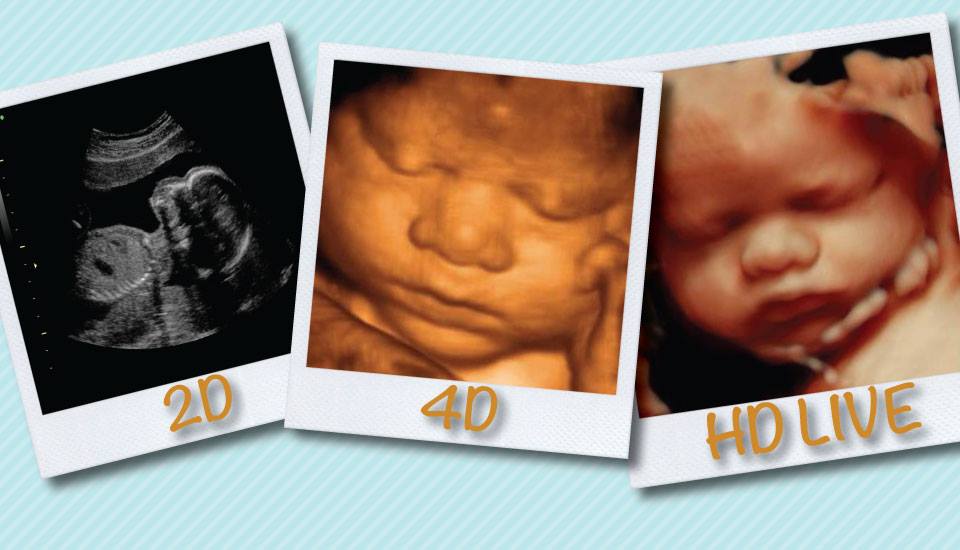

2D Ultrasounds – 2D ultrasounds are what most people think of when they imagine baby ultrasounds. These black and white photos are the kind that most doctor's offices provide, but you can get them from Kicks & Giggles as often as you'd like from eight weeks up until delivery.

3D Ultrasounds – 3D ultrasounds for babies are a big step up from traditional 2D ultrasounds because they give a much better idea of what the baby's face actually looks like. With these 3D baby scans, you'll be able to see the contours of your young one's face and start arguing about whose nose they have.

4D HD Ultrasounds – 4D HD baby scans take 3D ultrasounds to the next level by adding time — in other words, a video! You'll be able to see your baby move, all while enjoying their very realistic likeness. The traditional time for these images is 26 to 34 weeks but it's available from eight weeks on. Early on can be fun to see the whole baby jumping and moving around while later is fun to see the face with features that really reflect how they will look when born.